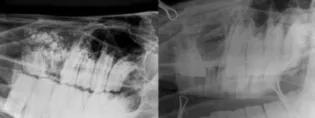

We have a dedicated radiography suite with a gantry-mounted Siemens Gigantos x-ray machine and AGFA computed radiography system which enables us to take extremely detailed, high-quality radiographs of the appendicular skeleton, thorax, head and neck. We also have light-weight mobile generators for use in the hospital and in our first opinion practice (DVEP); and the Cuattro II digital radiography system for immediate acquisition of images. If required, all radiographic images from a horse can be copied onto a CD and sent to the referring veterinary surgeon or insurance company.ImageIf required, all radiographic images from a horse can be copied onto a CD and sent to the referring veterinary surgeon or insurance company.Orthopaedic radiographyRadiography remains the backbone of lameness diagnosis, and high quality computerised radiography means that we get excellent images of the skeleton to maximise our diagnostic ability.Radiography of the headRadiography is an important part of the work up of many cases, particularly those involving the sinuses and/or teeth. The department has published widely on radiography of the equine head and has been responsible for developing innovative techniques in this field.Related LinksEquine orthopaedicsEquine soft tissue surgery This article was published on 2024-09-02